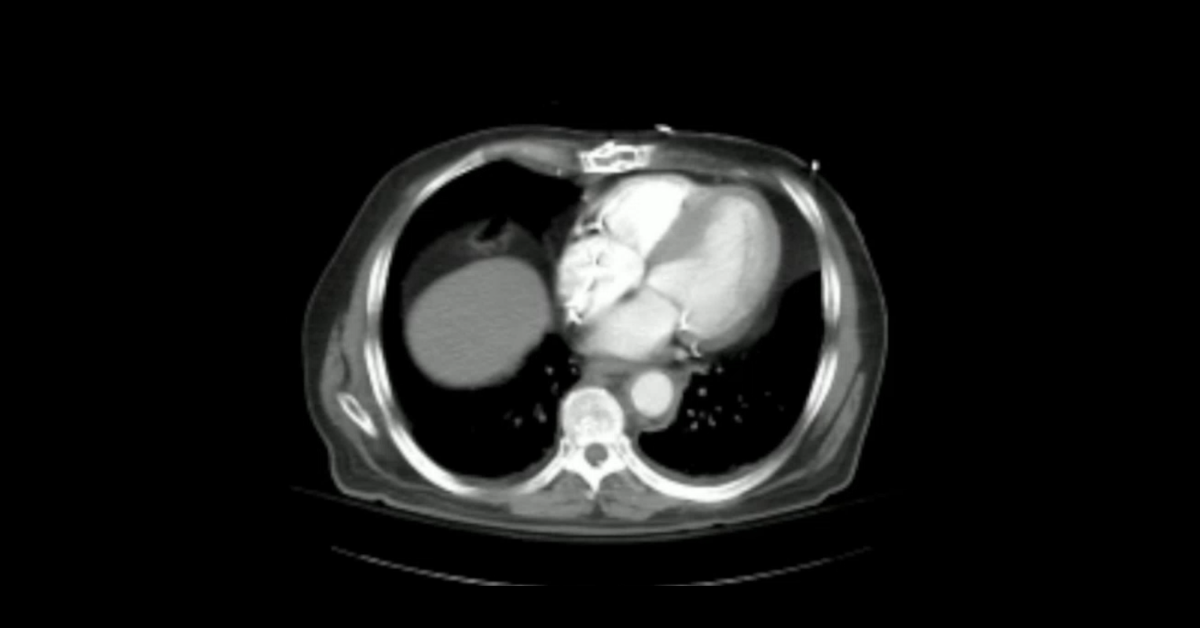

Cases of penetrating trauma to the aorta, with detailed description of imaging findings and potential complications.

1. Learn the appearance of aortic injury from penetrating trauma.

2. Appreciate the importance of identifying mediastinal hemorrhage and hemopercardium.

3. Understand the potential distraction the apparent vector of penetrating trauma can cause.